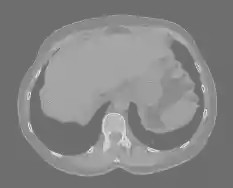

Cone-beam CT (CBCT) employs a flat-panel detector to achieve three-dimensional imaging with high spatial resolution. However, CBCT is susceptible to scatter during data acquisition, which introduces CT value bias and reduced tissue contrast in the reconstructed images, ultimately degrading diagnostic accuracy. To address this issue, we propose a deep learning-based scatter artifact correction method inspired by physical prior knowledge. Leveraging the fact that the observed point scatter probability density distribution exhibits rotational symmetry in the projection domain. The method uses Gaussian Radial Basis Functions (RBF) to model the point scatter function and embeds it into the Kolmogorov-Arnold Networks (KAN) layer, which provides efficient nonlinear mapping capabilities for learning high-dimensional scatter features. By incorporating the physical characteristics of the scattered photon distribution together with the complex function mapping capacity of KAN, the model improves its ability to accurately represent scatter. The effectiveness of the method is validated through both synthetic and real-scan experiments. Experimental results show that the model can effectively correct the scatter artifacts in the reconstructed images and is superior to the current methods in terms of quantitative metrics.